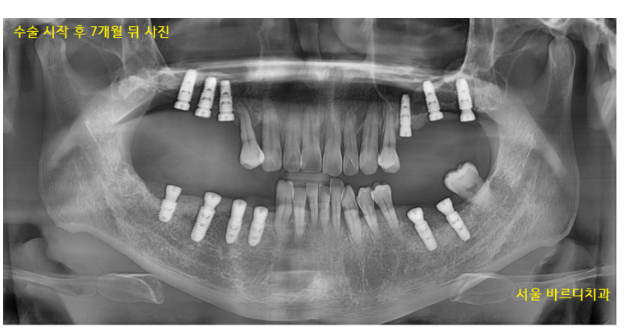

231218

그동안 치아 상태는 이런 모습이셨어요.

어금니라고는 단 2개 만 남아있었습니다.

오른쪽 1개 왼쪽 1개

식사가 얼마나 어려우셨겠어요~

뭐라도 드셔야 하시니 임시틀니로

식사하실 수 있게 도와드렸습니다.

240408

7개월이라는 길고 긴 고난의 시간을 겪고

길동 치과에서 치료를 끝내드렸습니다.